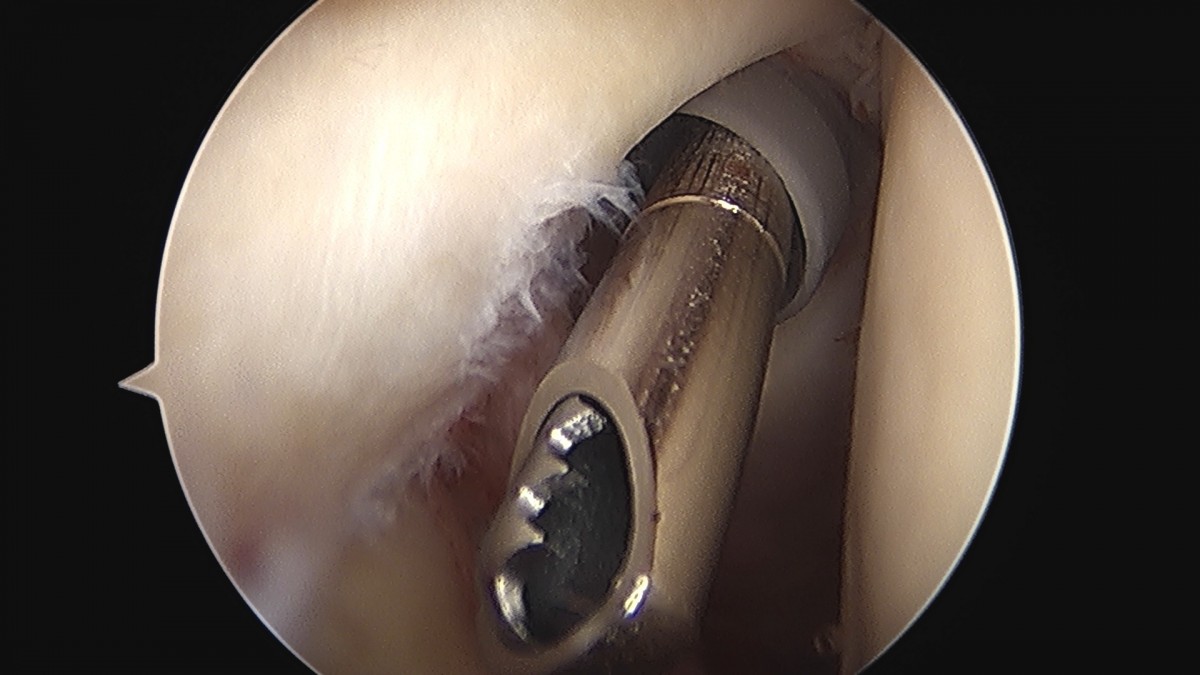

이재상원장님 어깨 견봉하 감압술 김선O 환자

dae765e4d9ac96aee867c9d6292d8784_1758004049_4756.jpg